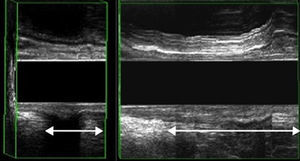

Descenso perineal por EEAD: descenso del puborrectal en la ecografía en máximo esfuerzo mayor de 2,5cm (fig. 4).

| 3.ª etapa | Reposo 3 s seguido de esfuerzo defecatorio máximo | Descenso del fascículo puborrectal | Síndrome del periné descendido (descenso>2,5cm) |